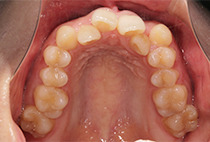

出っ歯と前歯のガタつきにお悩みだった20代女性の症例です。

金属アレルギーがあるため、メタルフリーで治療できる【インビザライン】による抜歯矯正を選択されました。

叢生、左右非対称咬合